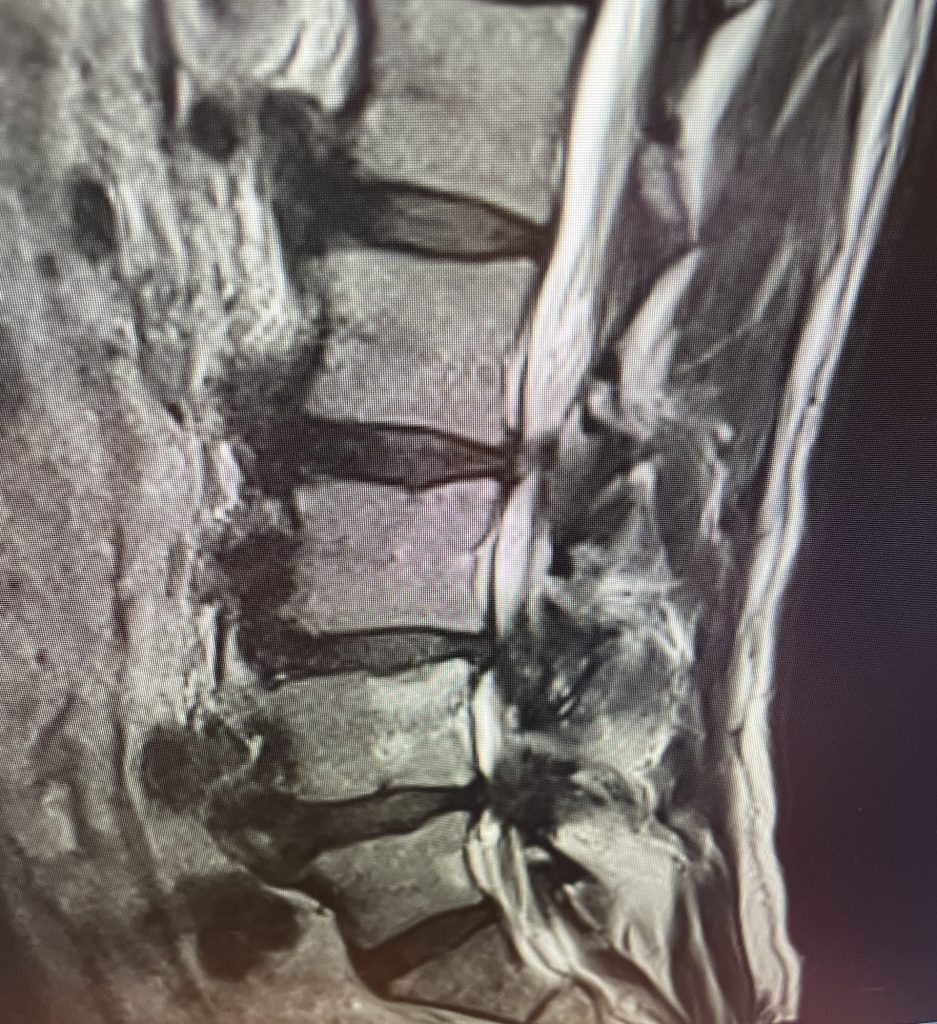

This 71 year-old male presents with a long history of progressive pain in the low back with radiation to both legs in the anterior thigh distribution, the left being worse than the right. He feels that his legs get weak. Standing and walking worsen the low back pain and lower extremity symptoms while sitting relieves the symptoms. He failed PT and epidural injections. Imaging studies revealed severe lateral recess stenosis do mainly to severed thickened ligament. He had severe lateral recess stenosis from L2-5 (Fig 4) as well as central stenosis. He also had a slight retrolisthesis at L3-4 and L4-5. He had on the left in particular a very enlarged protruded segment of thickened ligamentum in the subarticular recess at L3-4 (Fig 5) which was likely responsible for his left leg pain as the patient had symptoms of an L4-type syndrome. It was decided to perform a decompressive laminectomy from L2-5. Because of retrolisthesis it was decided to perform a noninstrumented onlay bone fusion or an in situ fusion from L3-5. In this case it was very important to decompress not only the thecal sac, but also the lateral recess with the thickened ligament at the point where the nerve makes its course into the forman. As a surgeon you must really undercut the facet joints to clear the lateral recess and feel how the nerve root with one’s instrument is being released as it enters the foramen. Postoperatively the patient had resolution of his leg pain, particularly on the left. In this case the most significant pathology was in the left L3-4 lateral recess, his symptoms and MRI findings correlated well which leads to the most successful operations.

Figure 4: Sagittal T2-weighted MRI demonstrating severe lateral recess stenosis from L2-L5 as well as slight retrolisthesis at L3-4 and L4-5.